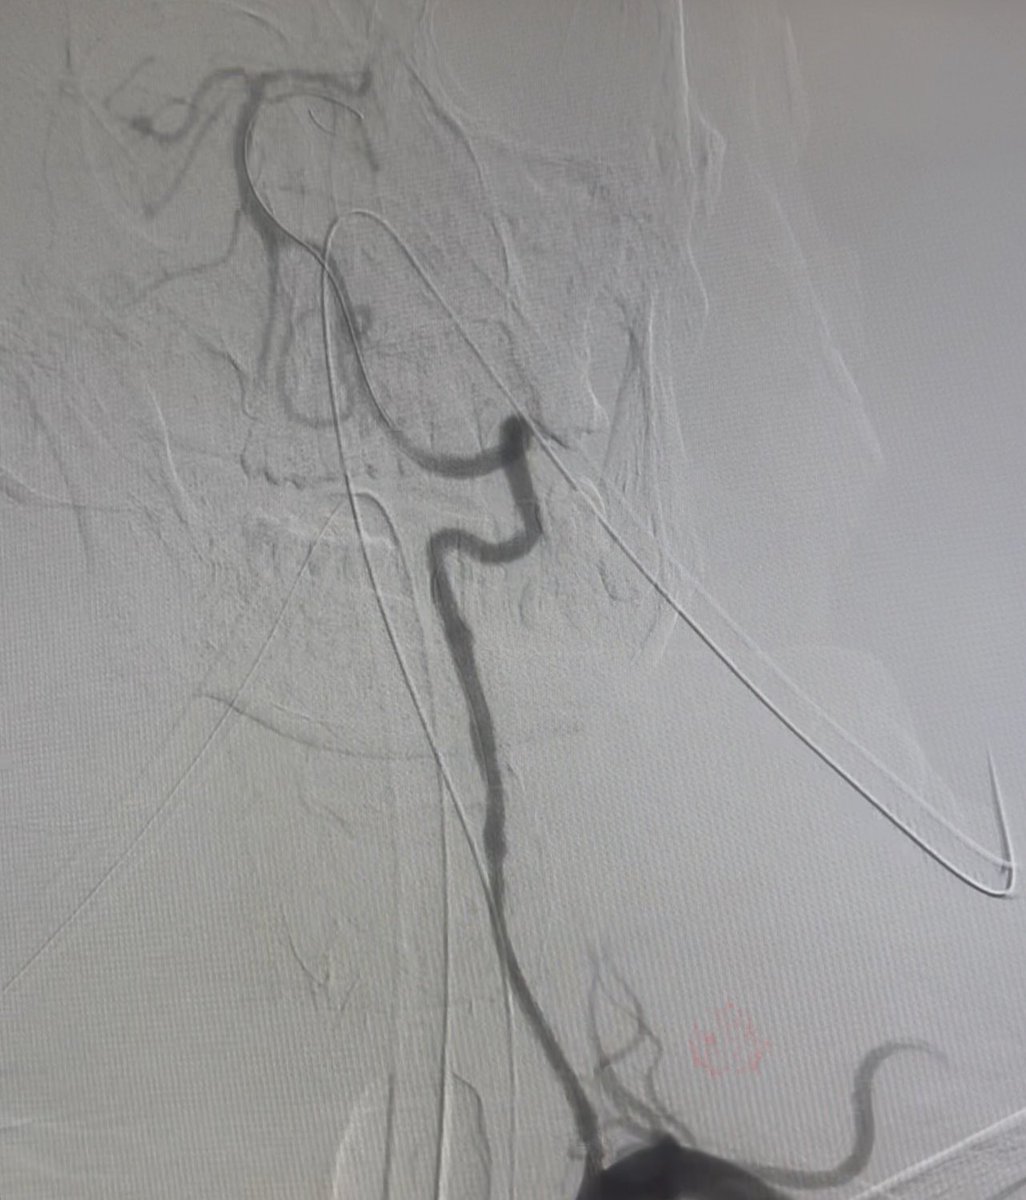

Successful carotid artery stenting in near total occlusion symptomatic stenosis case. 🧠 Timely intervention is key to stroke prevention. #Neurointervention #StrokePrevention #CarotidStenting #Endovascular

Successful carotid artery stenting in near total occlusion symptomatic stenosis case.

🧠 Timely intervention is key to stroke prevention.

#Neurointervention #StrokePrevention #CarotidStenting #Endovascular